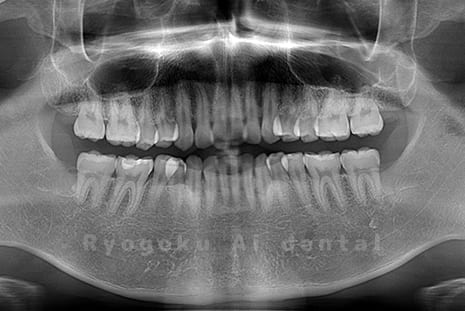

真っ直ぐ生えている親知らず

親知らずが真っ直ぐ生えているタイプです。

このタイプは真っ直ぐ生えていて咬み合わせに問題がなければ、抜歯しないケースもあります。ただし、虫歯になっていたり、痛みがあったり、咬み合わせが悪かったりすると抜歯をおすすめします。